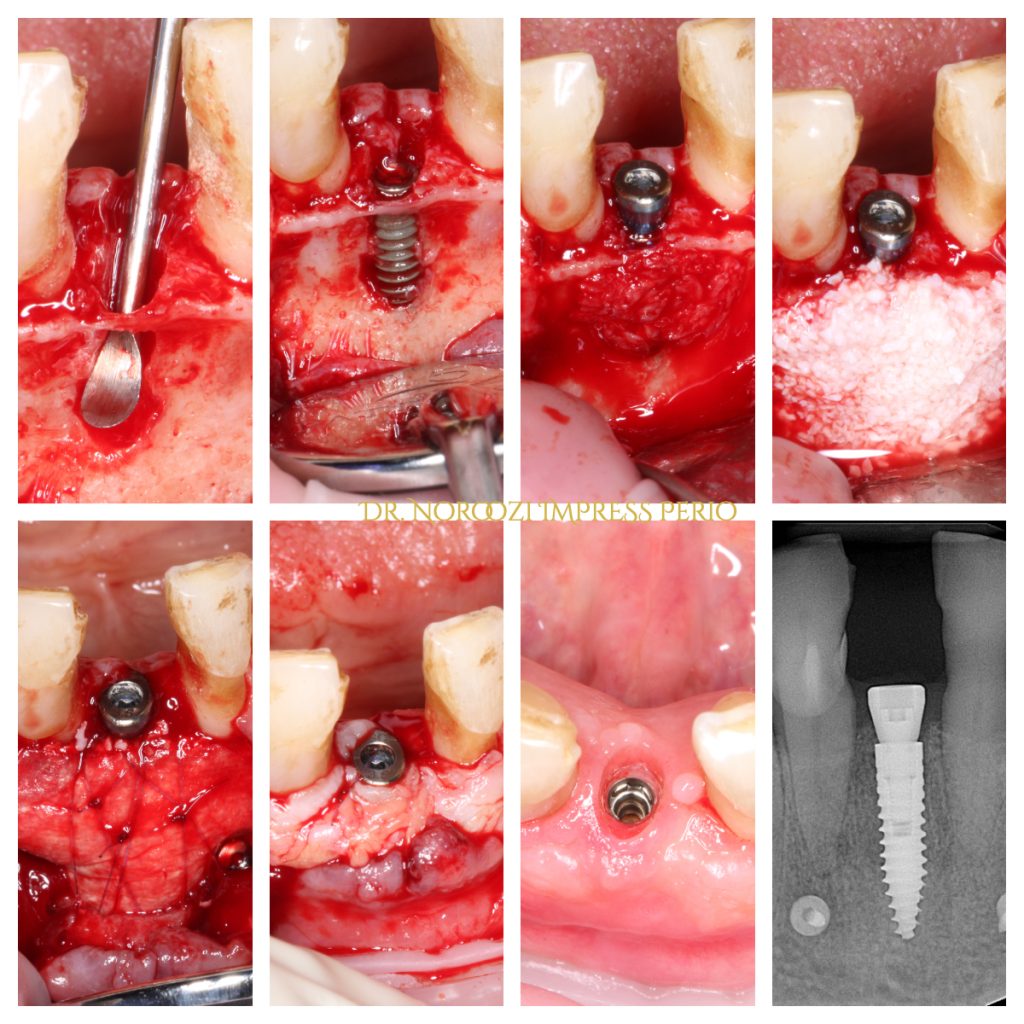

Immediate Implant Placement in Molar Extraction Site

immediate implant placement in molar site Dr. Noroozi

IMPrESS Perio Implant Center Dr. Noroozi Vancouver Periodontist Implant Specialist Burnaby BC